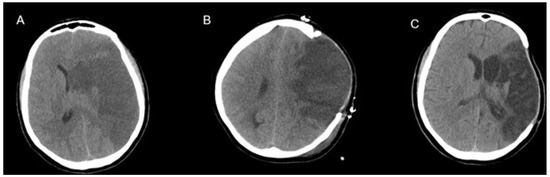

Illustrative Cases